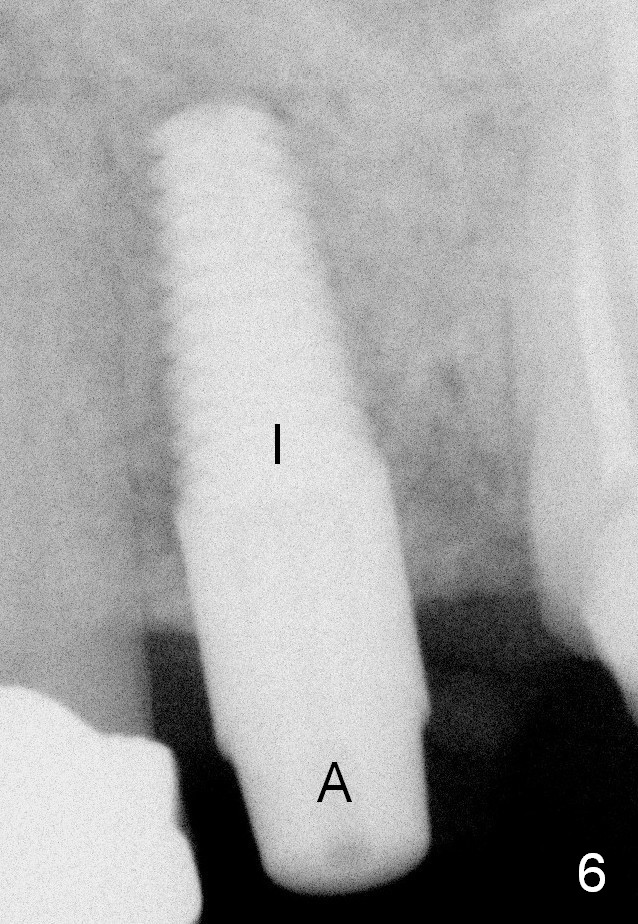

A 45-year-old lady is nervous about dental treatment. The missing tooth #13 was replaced by a 3-unit bridge. The latter is sectioned because the posterior abutment has caries. PA in Fig.1 is taken when root canal therapy and build up are finished. Fig.2 shows the wide edentulous area with a single-unit crown being tried in for #14. Osteotomy is initiated with the crown in place without cementation, since it is easy to determine the mesiodistal position (Fig.3 red lines). Without the crown in place, osteotomy tends to be distal. In this case, the osteotomy is later attempted to be moved distally with Lindamann bur and deepened to 14 mm from the gingival margin (Fig.4). A 2.5 mm reamer is being used at 50 RPM to increase osteotomy with difficulty. Drills have to used at high RPM instead (Fig.5 4x14 mm). A 4.5x14 mm tissue-level implant is placed with insertion torque >60 Ncm (Fig.6 I); a 4x3 mm abutment (A) is placed immediately for an immediate provisional. Fig.7 is taken 7 days postop to show the gingival recipient site formed by the provisional. The patient is so afraid of X-ray that the next one is taken 1.5 years post cementation (Fig.8). It appears that dense bone bundle forms between the crest and the 1st implant thread (adaptation functional change, arrowheads). The bone density continues to increase 2 years 8 months post cementation (Fig.9 *, 10); the bone has grown into the area between the 1st 2 threads (arrow).